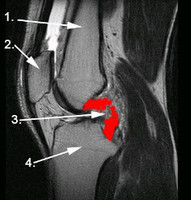

Kreuzband

Das vordere Kreuzband ist ein wichtiges Band zur Stabilisierung des Kniegelenkes. Im Falle eines Kreuzbandrisses ist in aller Regel ein muskuläres Aufbautraining zur Kompensation der Instabilität nicht ausreichend. In Folge der verbleibenden Instabilität kann es zu einer vorzeitgen Arthrose kommen. Daher wird insbesondere beim jüngeren Patienten eine vordere Kreuzbandersatzplastik zur Vermeidung dieser Folgeschäden

empfohlen.